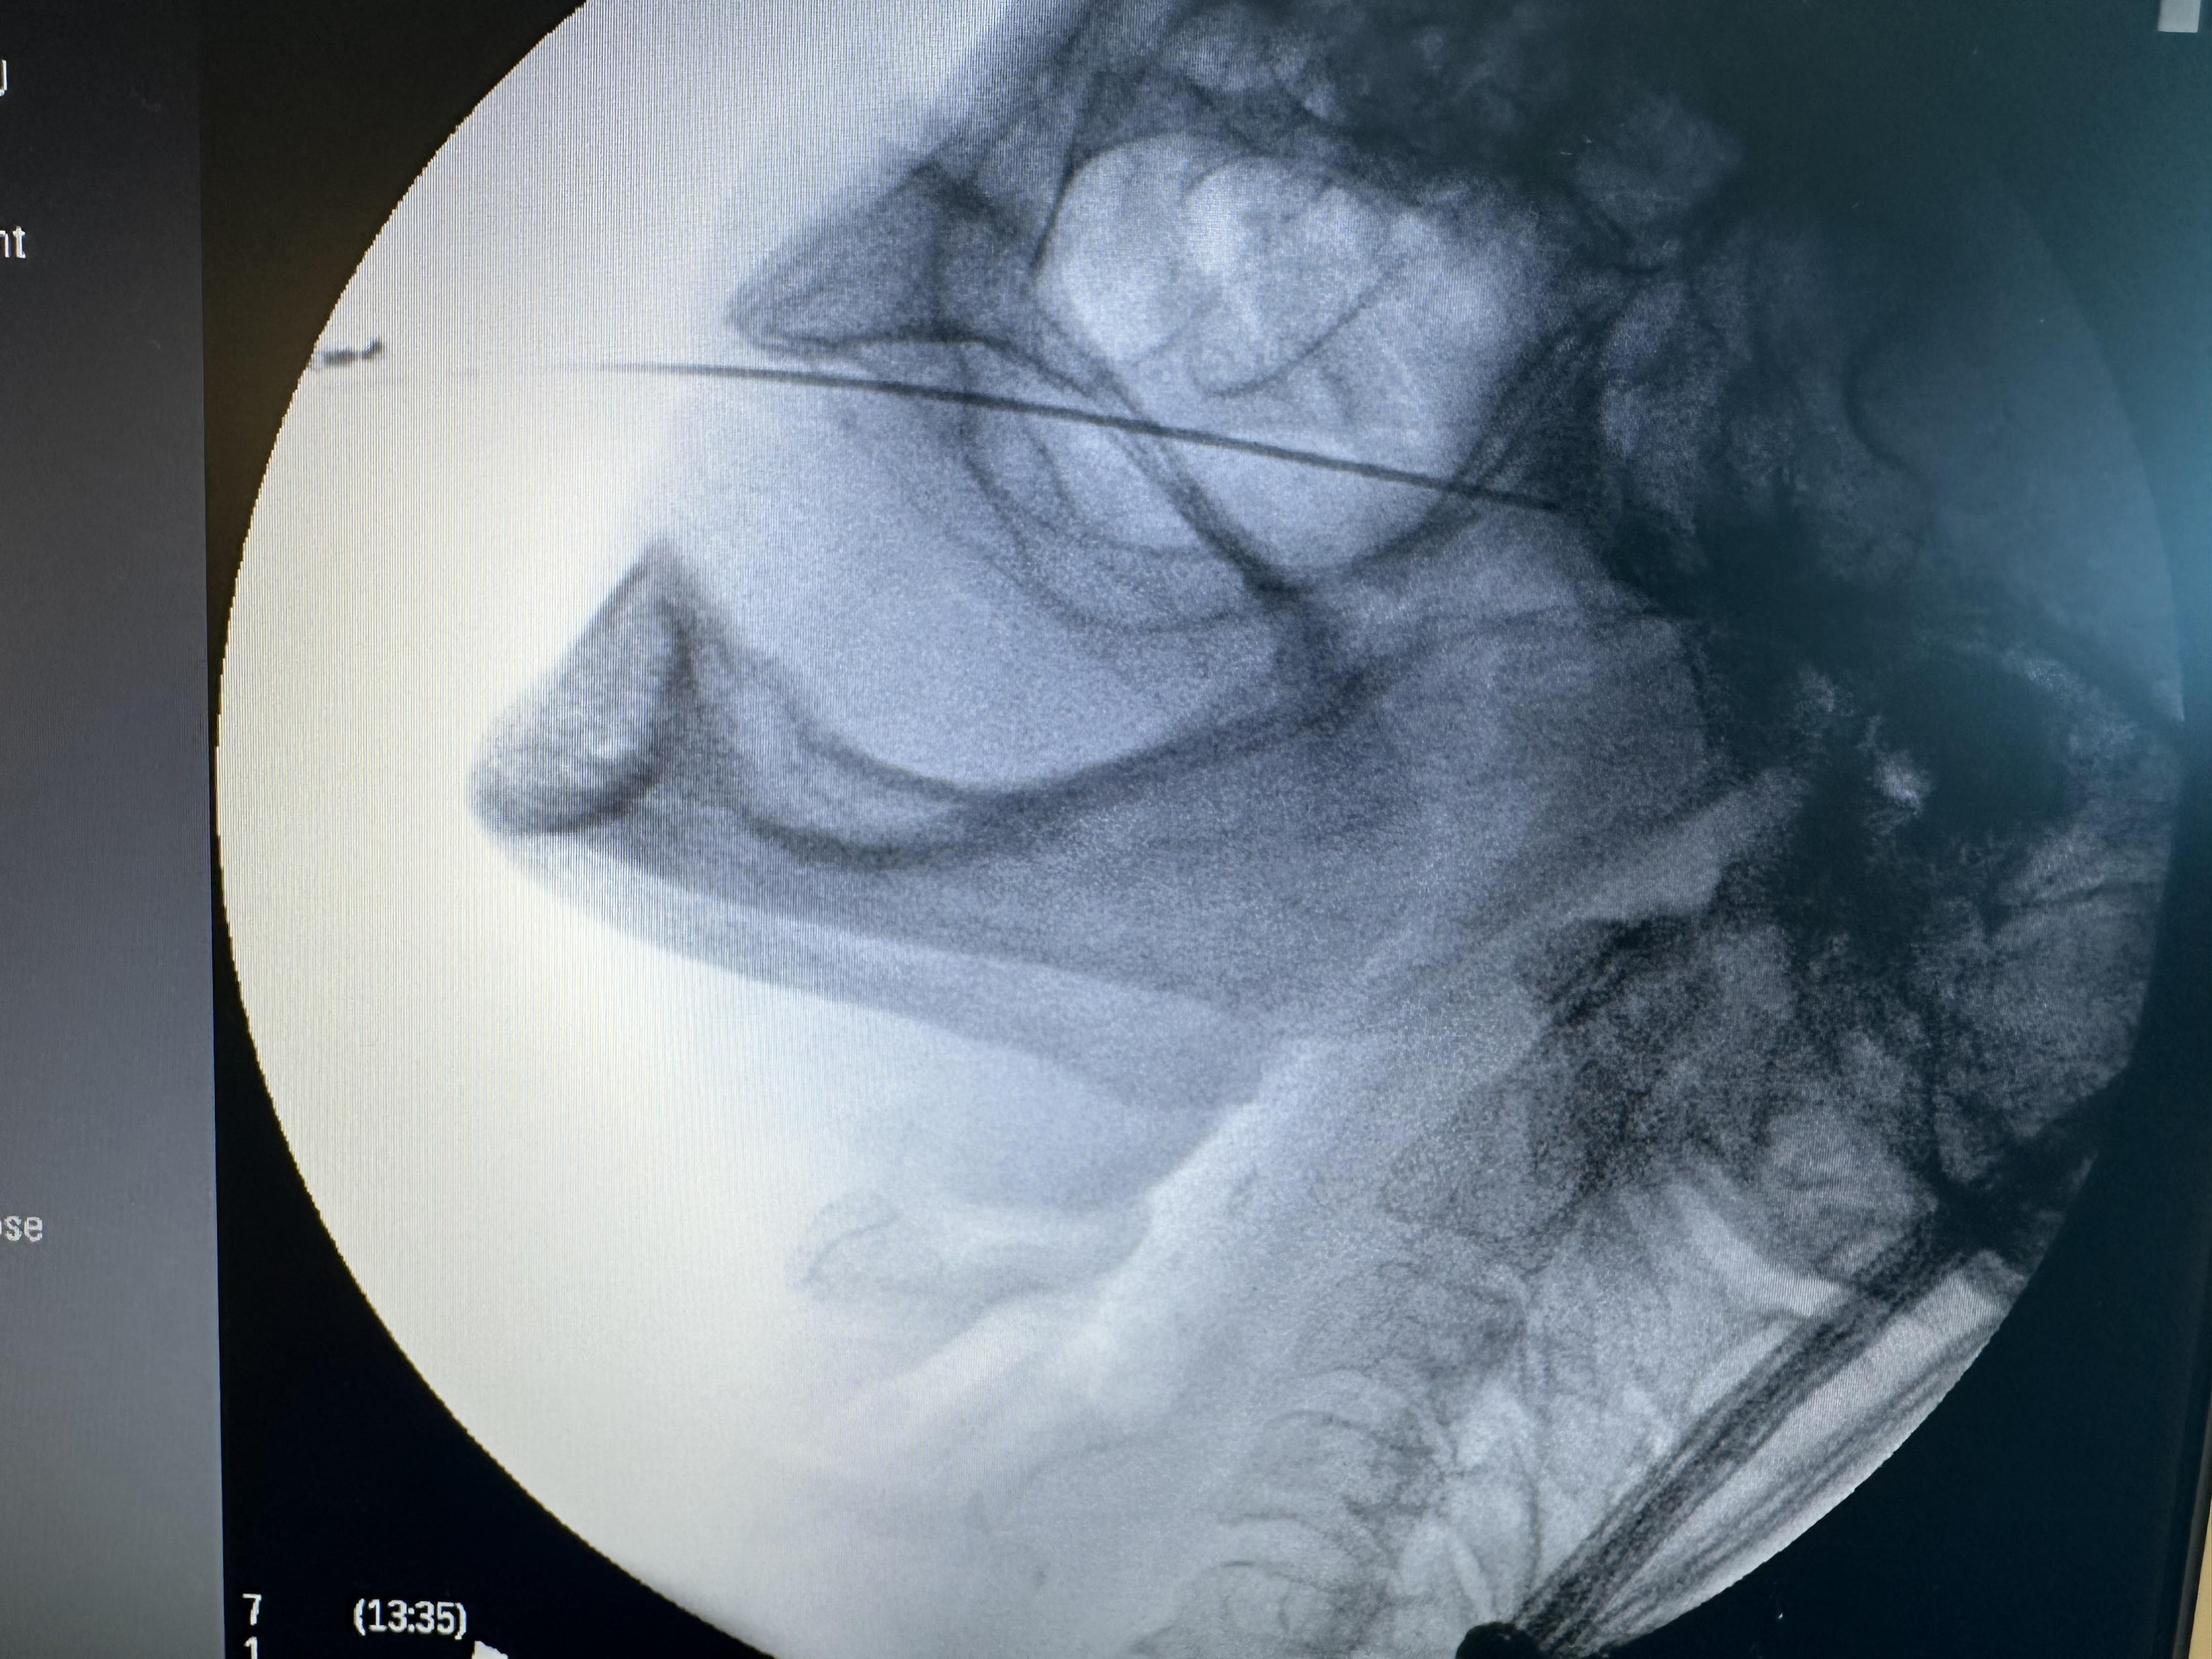

Given the patient’s refractory symptoms, medication intolerance, and elevated surgical risk, percutaneous cryoneurolysis was recommended. In April 2024, cryoneurolysis was performed at the ipsilateral foramen ovale targeting the V2 and V3 branches of the trigeminal nerve using a handheld cryotherapy device (iovera°, Pacira BioSciences, Inc., Brisbane, CA, USA). The procedure was performed under fluoroscopic guidance to confirm probe depth and alignment with the foramen ovale (Figures 1 and 2), and the patient tolerated the procedure well with no complications.